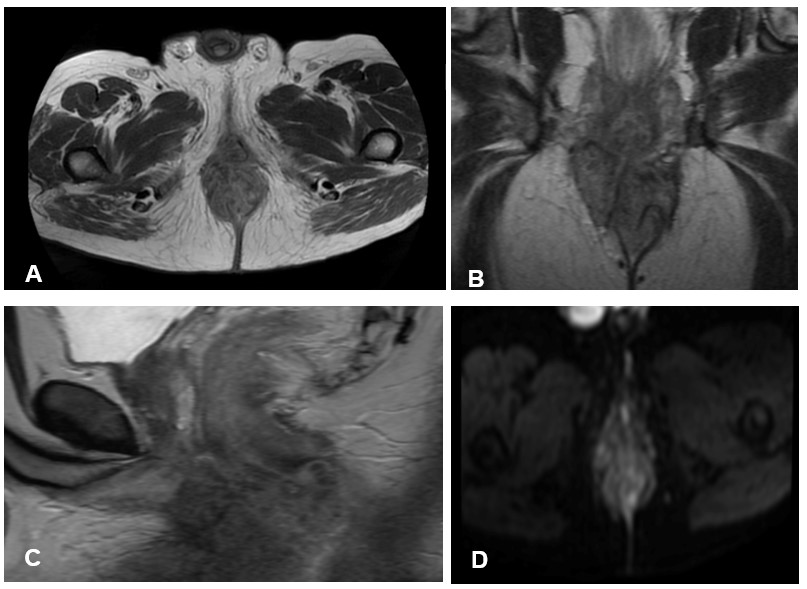

images A axial, B coronal, C sagittal in T2-weighted sequences, a tumor lesion of intermediate signal intensity is identified that compromises the four quadrants in a length of 78 mm and protrusion through the anal verge of 6cm, compromising the sphincter fibers. internal and external and the bulbar urethra and extends to the ischial fat. In the D axial DWI (Diffusion-weighted imaging) and E axial ADC images, there is marked restriction of the tumor mass.